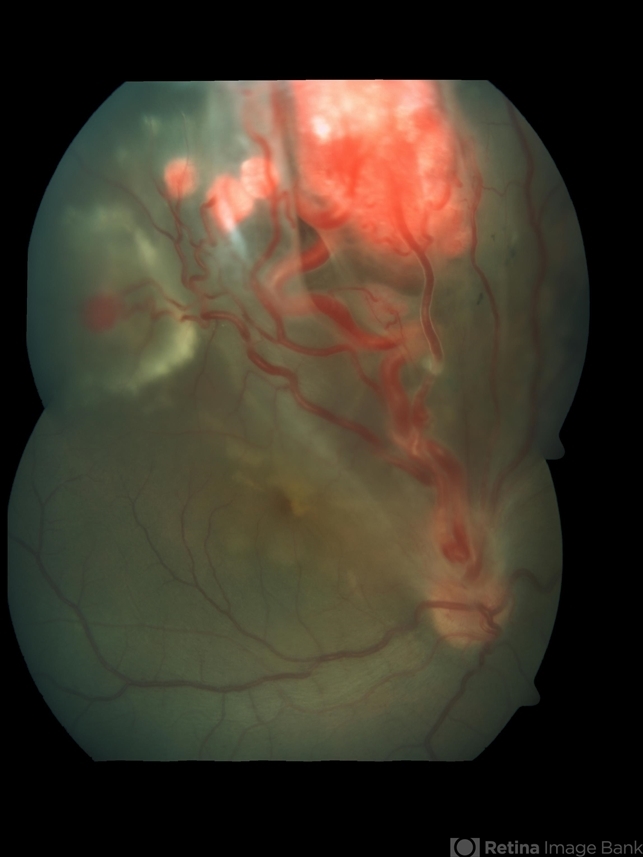

- Retinal Capillary Hemangioblastoma

- retinal capillary hemangioma, retinal angioma, Von Hippel-Lindau, tumor

- Fundus photograph of an 18-year-old Asian Indian male with multiple retinal capillary hemangiomas with sub retinal fluid.